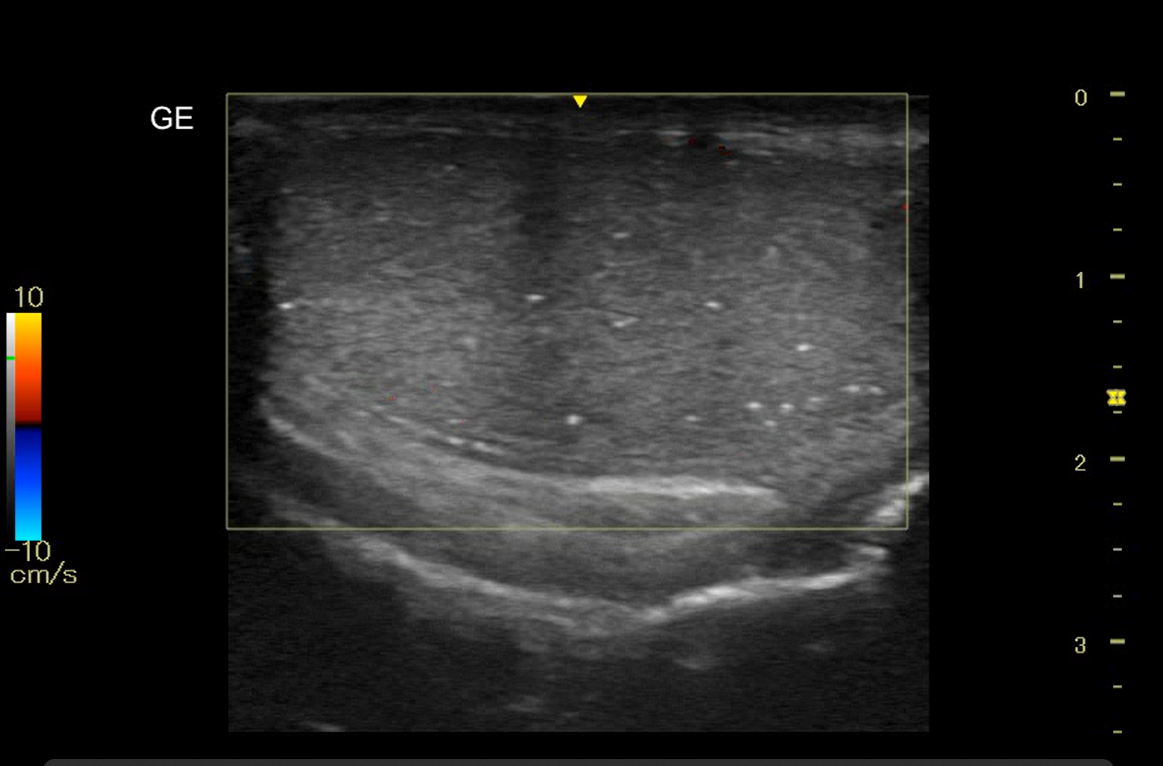

Realizamos ecografía clínica testicular: observamos ambos testículos con microlitiasis bilaterales puntiforme sin sombras acústicasen, en forma de cielo estrellado, vascularización normal, cabeza epidídimo izquierdo con leves signos inflamatorios, mínimo hidrocele.

Microlitisis testicular bilateral en contexto de Orquiepidimitis aguda. Diagnóstico diferencial con tumor testicular, torsión testicular, absceso testicular, hidátide.

La microlitiasis testicular es una entidad poco frecuente que se detecta de forma incidental durante una ecografía realizada por otros motivos como el caso de nuestro paciente. Se ha asociado con un mayor riesgo de desarrollar cáncer testicular y alteraciones de la fertilidad, como a otras patologías urológicas, como el varicocele, hidrocele, la orquiepididimitis, anomalías relacionadas con el síndrome de disgenesia testicular y el pseudoxantoma elástico. La ecografía es una herramienta diagnóstica esencial en atención primaria para la detección de las diferentes  patologías testiculares.